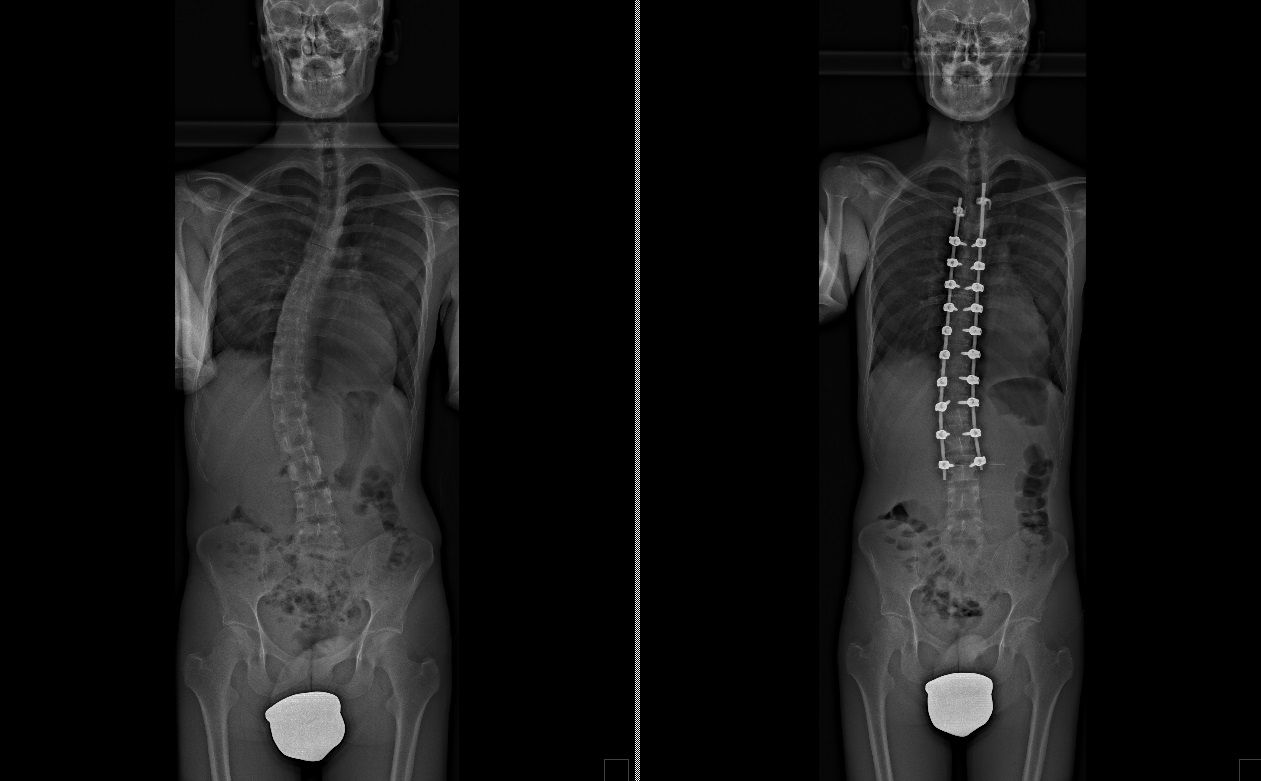

Laureato in Medicina e Chirurgia presso l'Università degli Studi di Napoli Federico II nel 2011, Specializzato in Ortopedia e Traumatologia presso la stessa Università nel 2017. Da subito ho dedicato i miei studi all'ambito della chirurgia vertebrale e della neurochirurgia. Infatti ho frequentato per 9 mesi tra il 2015 ed il 2016 i reparti di Neurochirurgia dell'IRCCS Neuromed di Pozzilli (IS) per apprendere le tecniche di trattamento delle Patologie della Colonna Vertebrale. Da allora il mio principale interesse è rivolto al trattamento conservativo e, dove necessario, chirurgico delle deformità della colonna vertebrale, sia dell’età dell’accrescimento che degenerative dell’adulto: scoliosi, dorso curvo, spondilolisi, spondilolistesi. Ulteriori campi di interesse sono il trattamento di lombalgia e lombosciatalgia, ernia del disco, stenosi del canale vertebrale, fratture vertebrali traumatiche o da osteoporosi (vertebroplastica), terapia del dolore osteoarticolare mediante tecniche mininvasive (radiofrequenze). Dal 2017 sono Consulente presso IRCCS Neuromed di Pozzilli (IS) con incarico di Responsabile del Centro per la Diagnosi e Cura delle Deformità Vertebrali e Scoliosi, dove svolgo la mia attività chirurgica in regime di convenzione. Svolgo la mia attività chirurgica in regime di solvenza e di convenzione assicurati presso la Clinica Ruesch di Napoli. Continuo costantemente la mia formazione con esperienze di perfezionamento nazionali ed internazionali. Infine, dal 2020 sono Docente per l'Università degli Studi di Roma "La Sapienza".

• Chirurgia vertebrale

Foto e video